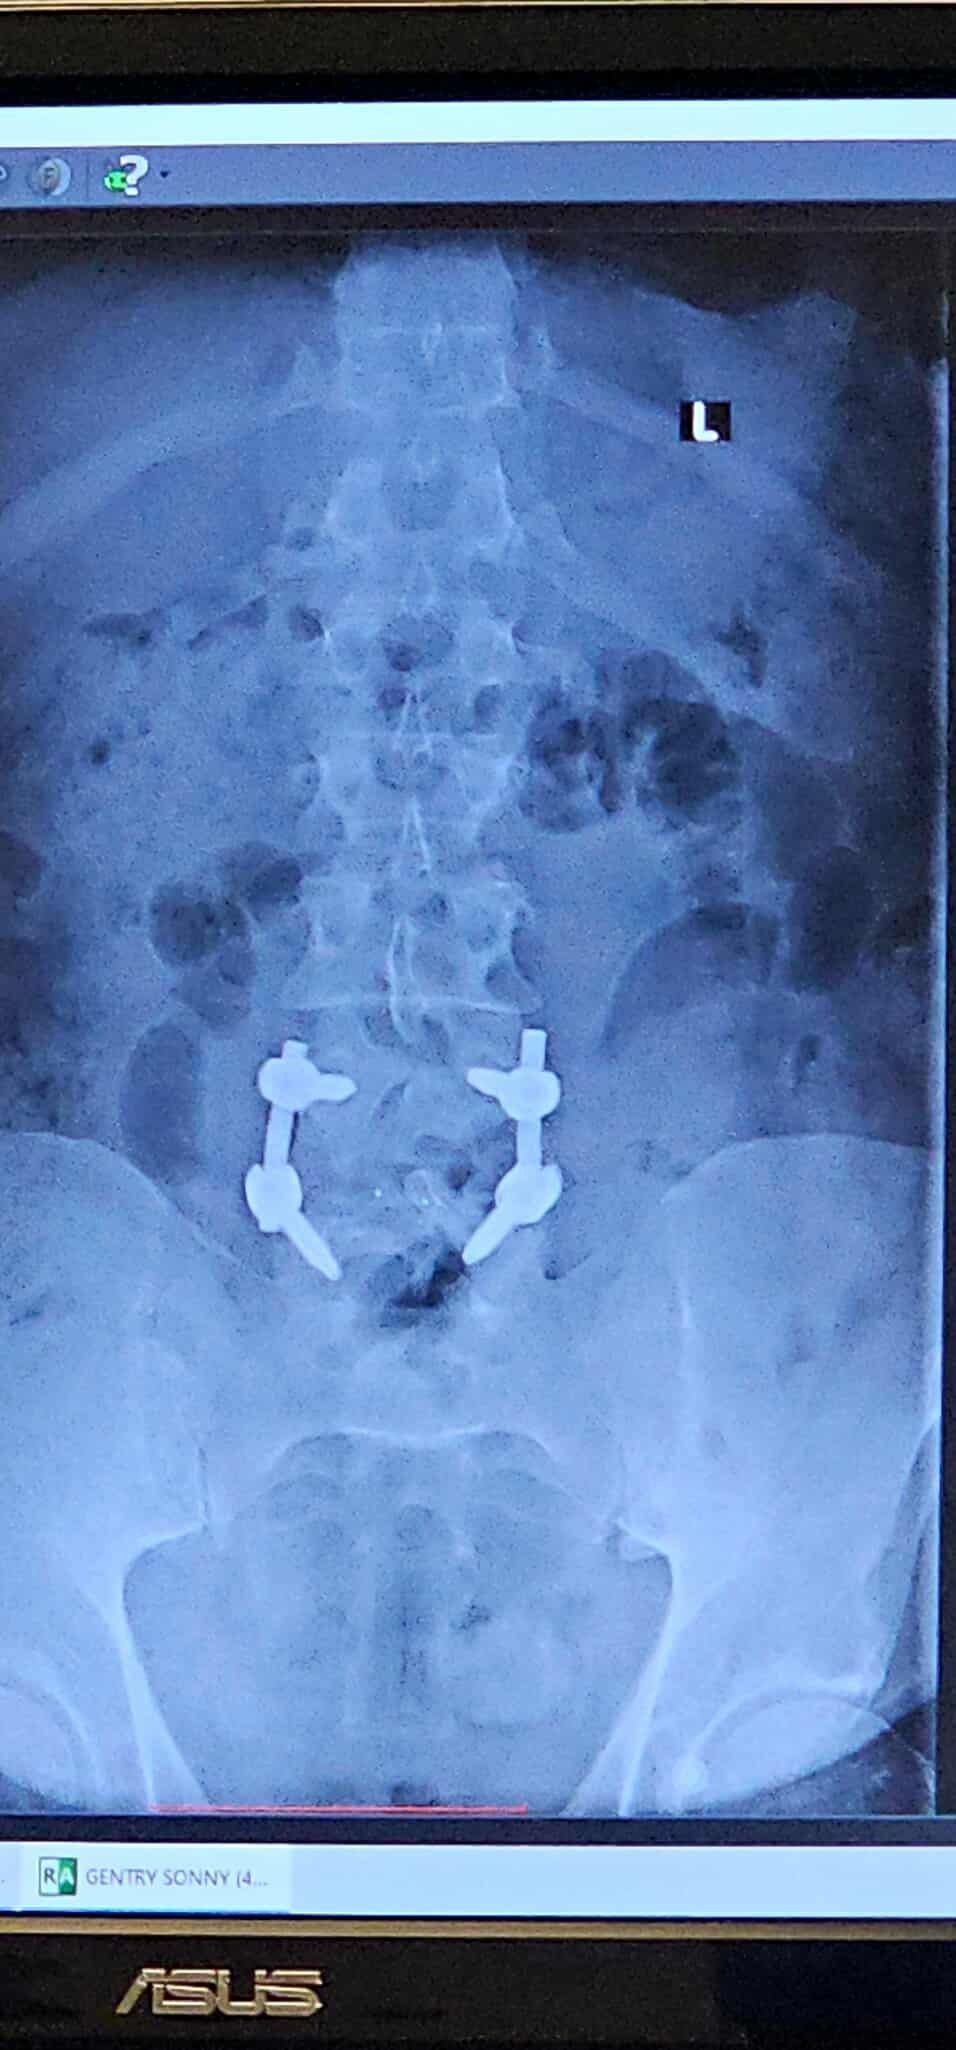

My name is Sonny Gentry. I was in a wreck 3 years ago at no fault of my own at 70 mph. As time passed by, my neck and lower back began to deteriorate. After waiting a very long time, I finally had surgery on July 15th, 2024, and that was a complete fail. I am only able to stand for 30 minutes at a time, and meds only help very little. Just really needing help with bills and meds as I am unable to work after all these years of working. Please feel in your heart to help. If CashApp $southerneuf81 or Venmo @sonny-gentry25 is better for you, then that's great too.